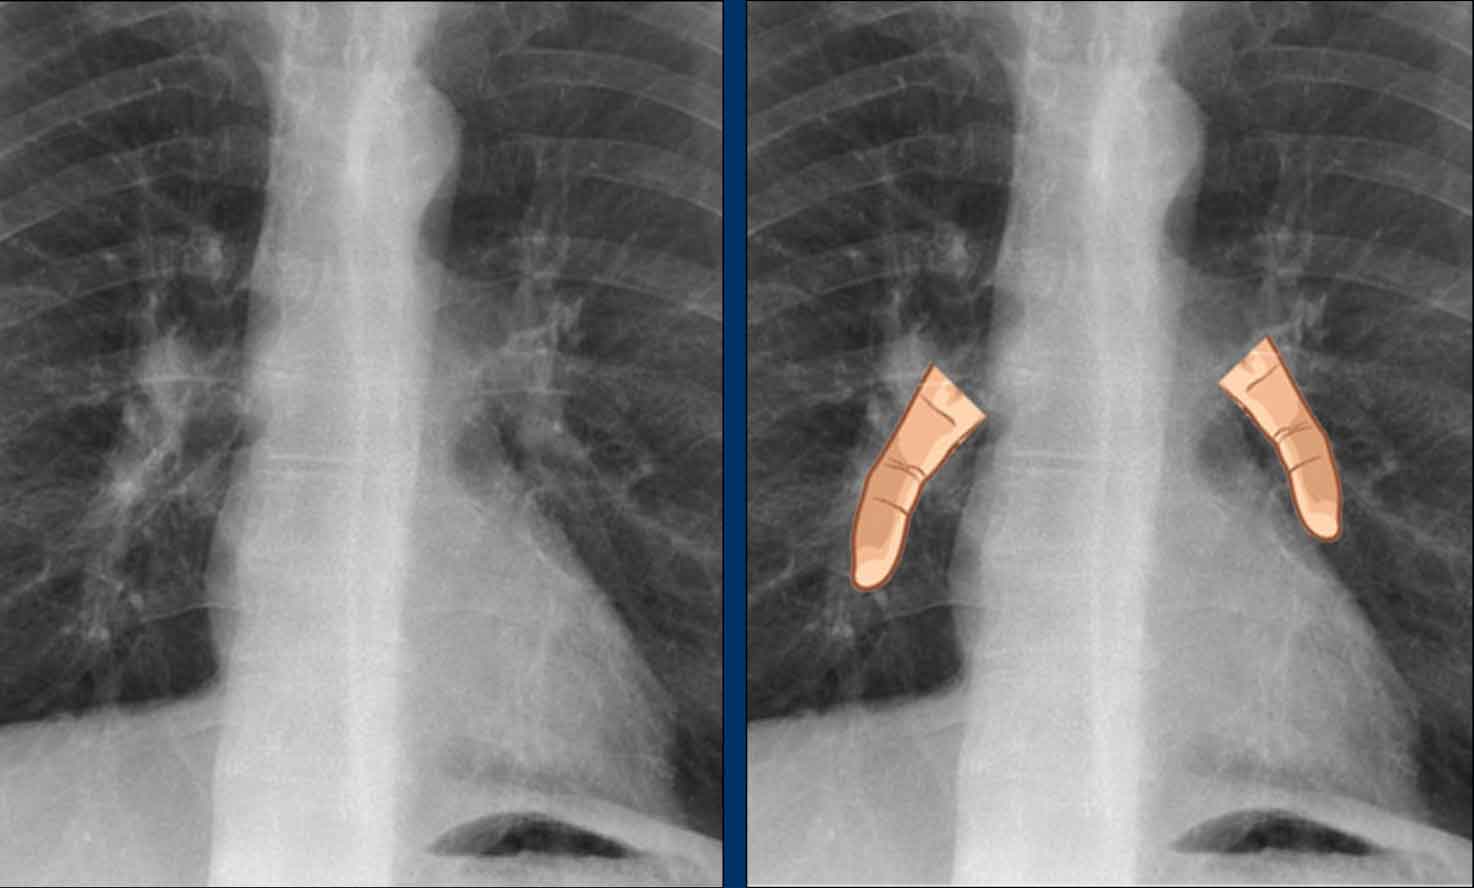

Another anatomical variant involves an accessory articulation at the anterior first rib (arrow).

At the junction of the bony and calcified cartilaginous segments, a pseudoarticulation may simulate a pulmonary nodule or mass on frontal imaging.